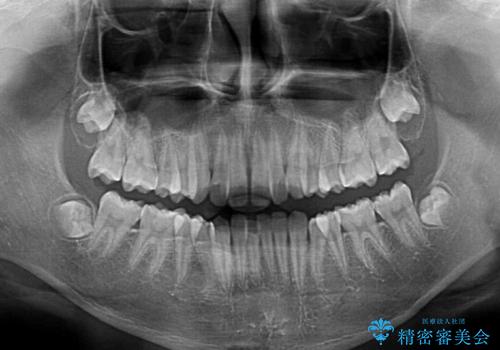

- 前歯のクロスバイトを気にして来院された患者様です。

中学生であることから、治療期間を短縮できると判断し、ワイヤー矯正にて短期間で治療を行うこととしました。

叢生のため磨き残しの多い歯列でしたが、1年弱で治療を終了でき、磨き残しや歯肉の腫れが著しく改善されました。